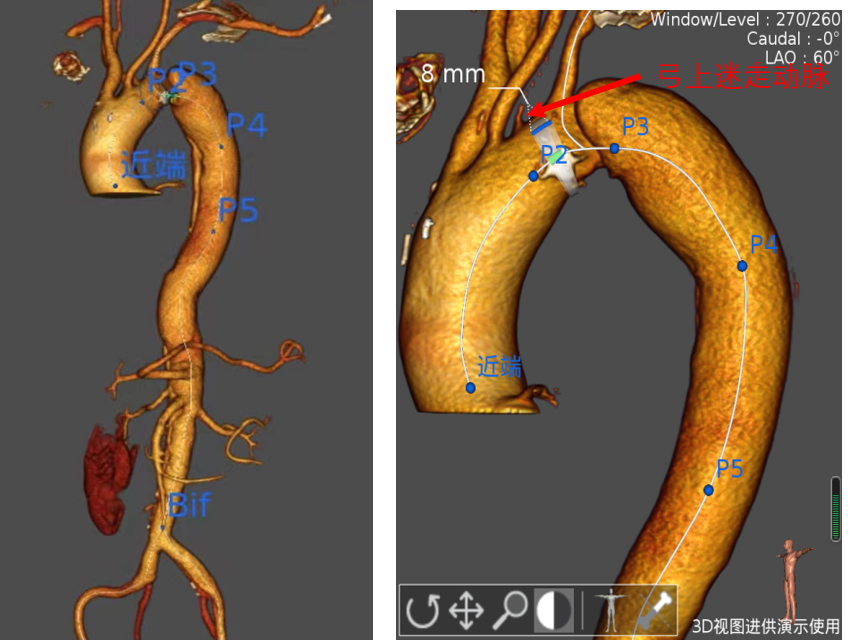

(术前3D模型显示,患者为B型主动脉夹层,弓上有4个分支动脉,且左锁骨下动脉与迷走左椎间距8mm,破口长度约30mm,手术对支架定位要求高。)